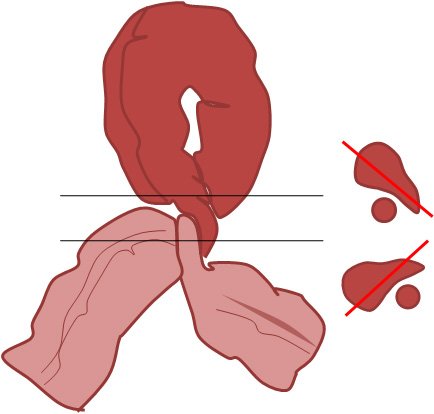

Esquema que explica la aparición de la marca X en un sigma volvulado.Las líneas negras indican los planos de corte. A la derecha se muestran las secciones axiales del sigma. En cada corte vemos una zona del sigma más colapsada y otra más dilatada cuya orientación es distinta a la del otro plano (líneas rojas).

Esquema que explica el Signo de la pared divisoria. Se trata de una volvulación incompleta del sigma, en la que existe una aparente separación de dos paredes del sigma por grasa mesentérica. Esto ocurre en la zona de rotación de un asa de sigma sobre sí misma.